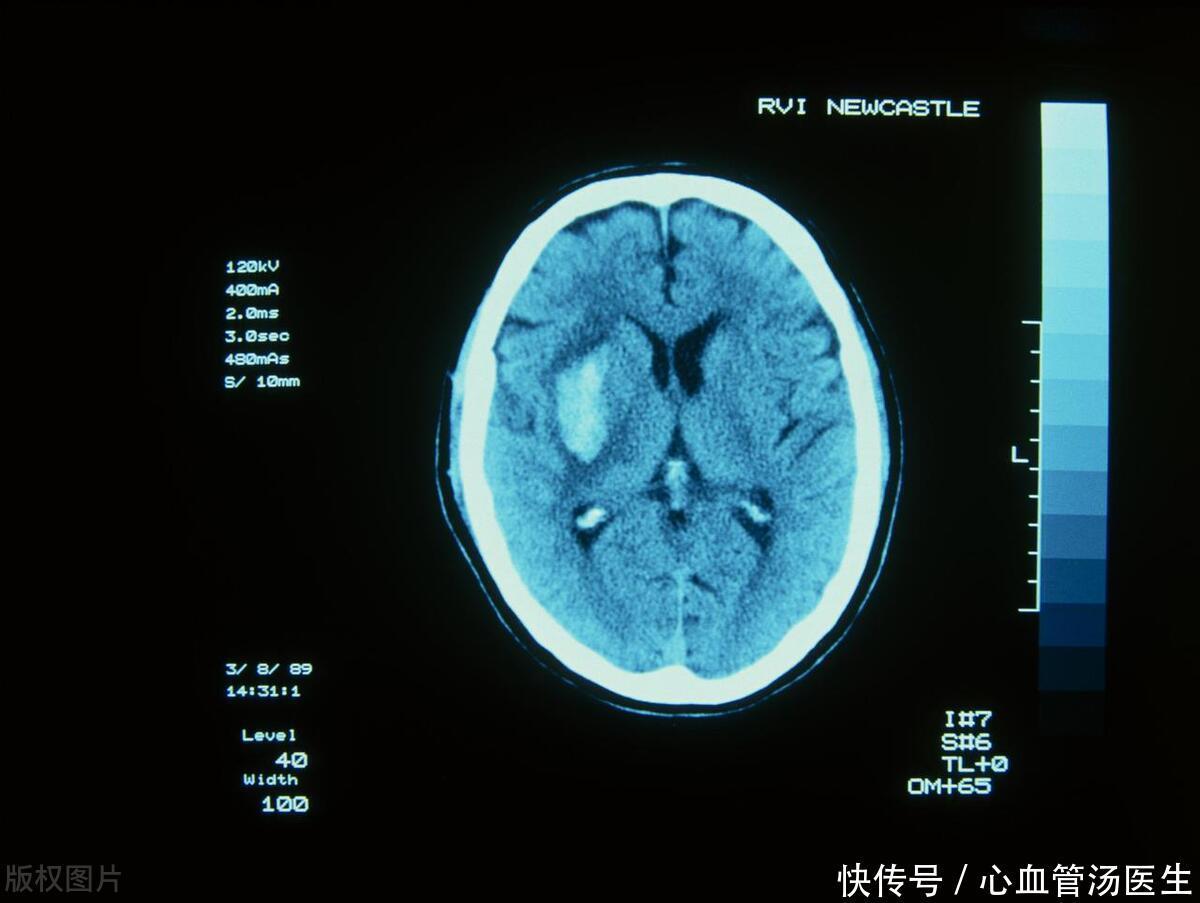

高血压会出现5个严重并发症,注意预警信号,做好3点预防